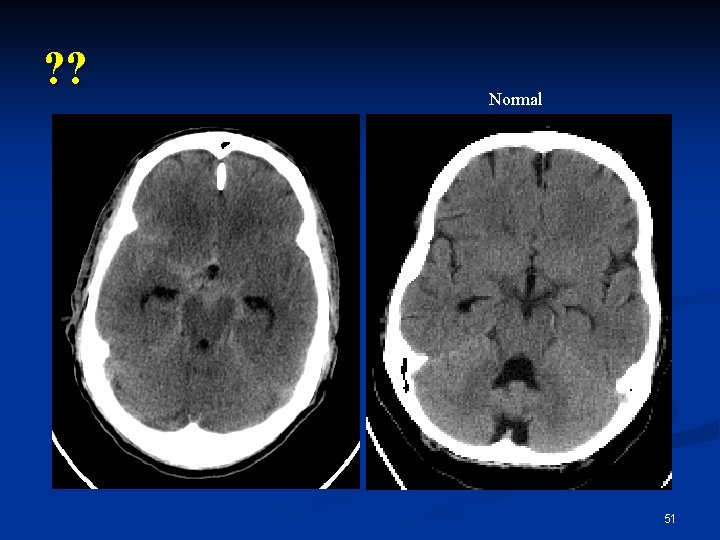

? ? Normal 51